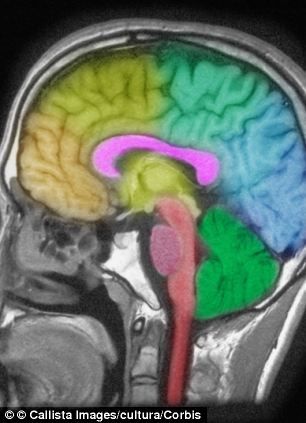

新浪科技讯 据国外媒体2日报道,你是不是有过这样的感觉:一晚上没睡好,第二天起来就觉得头好像被什么东西打了一样。科学家说,这不是危言耸听。一项新研究显示,只要一晚上不睡觉,你的大脑就会发生变化,影响和头部遭到重物打击一样。

这些科学家表示,研究中接受检查的健康年轻人表现出体内相同化学物质剧增的迹象。这些化学物质表明大脑受到伤害。瑞典乌普萨拉大学教授克里斯蒂安-本尼迪表示,化学物质——神经原特异性烯醇化酶(NSE)和S-100蛋白是脑震荡等脑损伤的生物标记。

这位科学家指出:“我们发现,在一晚上没睡觉的研究组中,这些化学物质在血液中的水平明显升高。虽然这个结果没有达到头部外伤造成的影响,但依然十分明显。睡觉时,大脑自己净化有毒物质。神经原特异性烯醇化酶和S-100蛋白的增加是对这些物质作出的反应。”

本尼迪说:“以前的研究表明大脑用睡眠来净化自己。我们的这些发现支持这个观点。以前还有研究显示,睡眠不足和老年痴呆症、帕金森氏病以及多发性硬化症危险的增加有关。我们的研究可能支持这个结果。失眠后血液中神经原特异性烯醇化酶和S-100蛋白水平的升高可能表示,没有得到足够睡眠促使脑组织的丧失。”